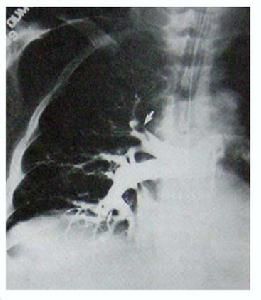

4.支氣管造影隨著胸部CT及纖維支氣管鏡的廣泛套用,現已能夠對直徑僅幾毫米的氣道進行直視觀察。加上支氣管造影檢查的操作過程,具有造成病人低氧和支氣管痙攣的潛在危險,大咯血病人往往難以耐受。因此,對於近期或活動性咯血病人而言,其診斷價值相當有限。目前,支氣管造影主要用於:①為證實局限性支氣管擴張(包括隔離的肺葉)的存在;②為排除擬行外科手術治療的局限性支氣管擴張病人存在更廣泛的病變。